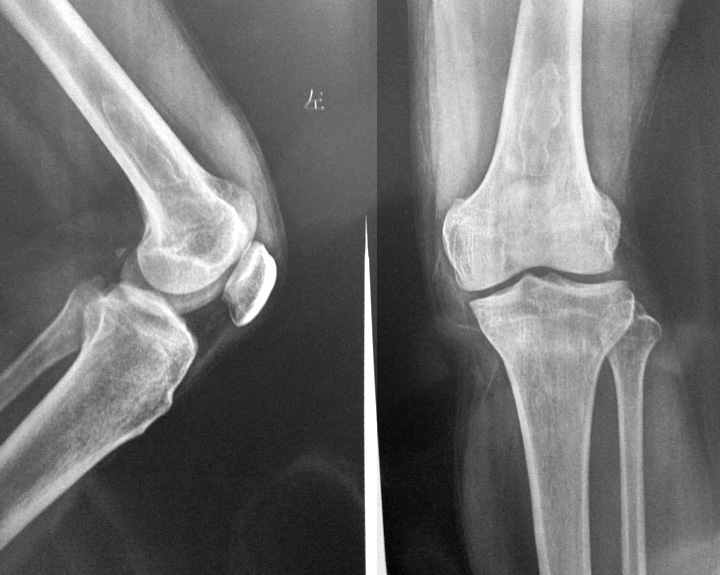

标题: X5552:左股骨下端病变。 [打印本页]

男性41岁,膝扭伤拍片发现股骨下端病变,以前无症状。

股骨下端骨梗死。

骨梗死不是一个独立的疾病。好发于长骨的两端,尤以股骨下端、胫骨上端和肱骨上端多见。早期x线片上无任何表现。当病变进入修复期时出现异常x线征象。

1、骨干—干骺端型 多见,于骨髓腔梗塞区先出现骨质疏松、吸收、密度减低,周围为钙化或骨化所包绕,与正常骨界限清楚,随病变进展,其间逐渐出现不规则钙化及骨化影,密度极高,边缘清楚,期间或周围有密度减低区,骨干及骨皮质多无异常。病灶常为对称性。

左股骨下段见斑片密度降低区,其周见钙化影,与外伤有关故考虑骨梗